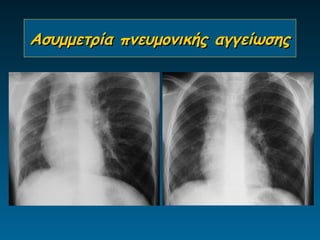

Ασυμμετρία πνευμονικής αγγείωσης